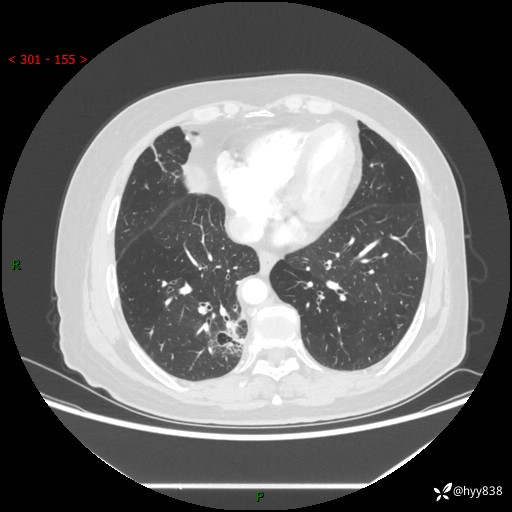

胸部CT肺窗(平扫外院)